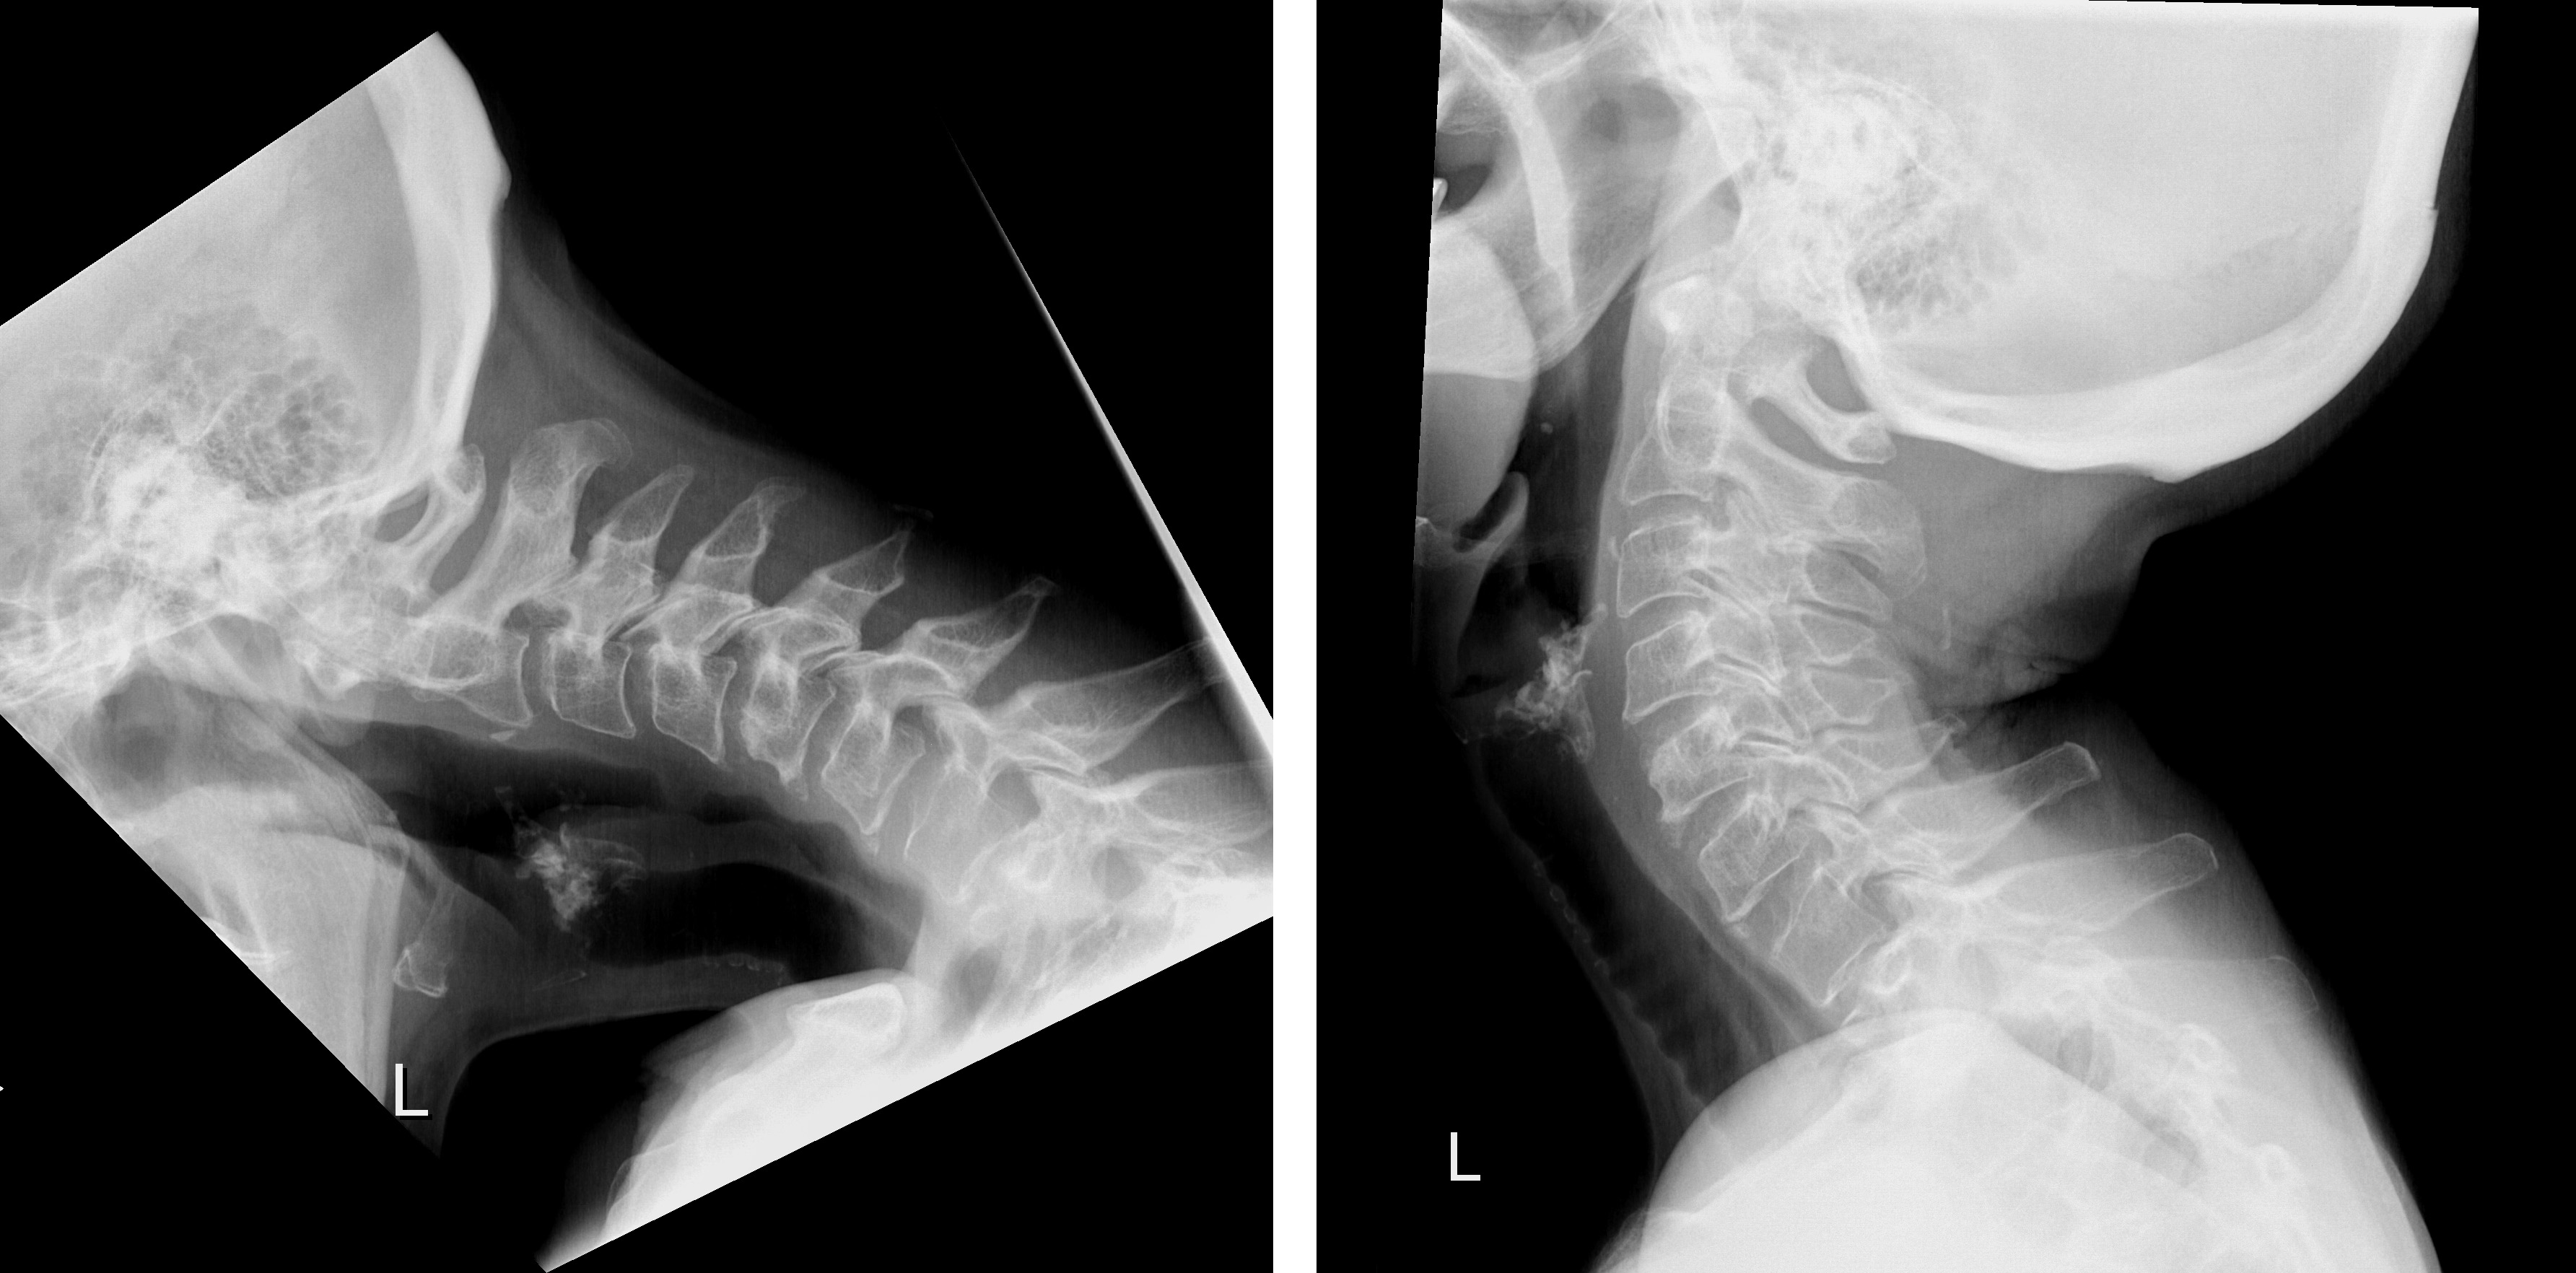

Dropped Head Syndrom (DHS), der «fallende Kopf», ist ein seltenes Leiden, das eine breite Differentialdiagnostik erfordert. Das DHS hat erhebliche Auswirkungen auf die Gesundheit und Lebensqualität der Betroffenen. Die Kopfhaltemuskulatur ist derart geschwächt, dass die Patientinnen und Patienten den Kopf nicht aufrecht halten können. Bisher war eine grosse Versteifungsoperation im Bereich der Hals- und Brustwirbelsäule die einzig mögliche Behandlung des DHS.

Prof. Mazda Farshad, Chefarzt und Direktor des Universitären Wirbelsäulenzentrums Zürich der Universitätsklinik Balgrist, und sein Team haben eine neuartige chirurgische Technik entwickelt, die erstmals eine erfolgreiche Behandlung des DHS ohne Versteifung ermöglichte. Mit der «Occipitopexy» genannten Methode wird der Kopf mit Ligamenten und Bändern an die Wirbelsäule befestigt. Der 68-jährigen Patientin geht es heute, eineinhalb Jahre nach der Operation, immer noch viel besser, sie lebt nahezu beschwerdefrei. Damit ist eine weniger einschneidende und vielversprechende Behandlung entstanden, die das Leiden der Patientinnen und Patienten lindert, ohne dass die Lebensqualität durch eine Versteifung beeinträchtigt ist.